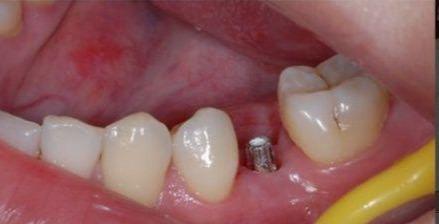

種植牙做法:在牙床上植入一個(gè)人工金屬「牙根」,待牙根與牙床穩(wěn)固之后,再在上面裝上一個(gè)烤瓷牙。種植的牙齒可以基本取代原本真牙的功能,不需要依靠別的牙齒。好處就是,單獨(dú)成為一個(gè)個(gè)體,和真牙一樣。

種植牙時(shí)間:調(diào)節(jié)時(shí)間長(zhǎng)啊,掉牙了等至少3個(gè)月——第一次就診,拍片做ct,醫(yī)生診斷,你要選擇種植體,預(yù)約一次手術(shù)時(shí)間——一次手術(shù)成功等兩個(gè)周拆線——拆完線等4到6個(gè)月二次手術(shù),植骨要等6個(gè)月,——然后是二次手術(shù)后等兩個(gè)周牙齦成型,種植體連上基臺(tái)和牙。

種植牙:種植牙則需要做不少檢查,嚴(yán)重依賴醫(yī)生技術(shù)(種植牙有很多風(fēng)險(xiǎn)因素,一旦遇到一無(wú)所知的醫(yī)生盲目植入,失敗造成的損失,經(jīng)濟(jì)事件肉體和精神上的都很大。